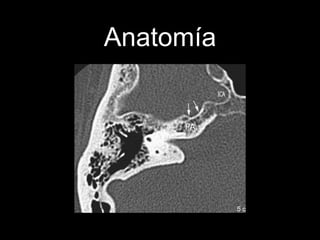

Anatomía.

Anatomía